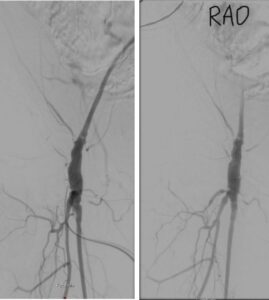

2-TEA-dan sonrakı angioqrafiya və bovin plastika materialının 2 proyeksiyada görüntüsü